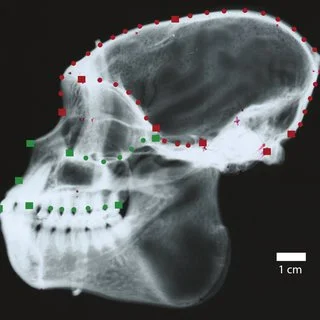

Es muy importante entender que la modificación de las estructuras óseas por la mano del hombre ha sido una práctica constante y continua en diversas culturas, por ejemplo, cito a tribus africanas en donde modificar el cráneo y culturas japonesas donde modificar los pies resultan símbolos de estatus, poder o belleza. A manera de tratamiento para estructuras hipo o hiperplásicas también es frecuente bajo el entendimiento de que se redirecciona el crecimiento más no se detiene, bajo ese concepto entiendo que la ortopedia maxilar se basa en comprender hacia dónde y como crece la cara del individuo, así como los factores que lo regulan, apoyándose de estudios cefalométricos como B. Jarabak, McNamara, Steiner, entre algunos más.

Les dejo un artículo que considero importante en el entendimiento de síndromes con el desarrollo subsecuente de dismorfias faciales como el paladar hendido. Espero sea de tu agrado.